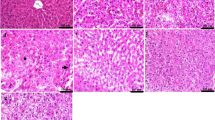

Histopathological studies

Histopathological examination of the brain, liver, and spleen tissues derived from all experimental groups is shown in Fig. 3. Microscopic examination of the brain tissue from group 1 (Fig. 3a1 and a2) revealed mild gliosis in the cerebral cortex with marked distension of the perivascular spaces. The striatum showed gliosis along with edema. Regarding the brain tissues from group 2 (Fig. 3b1 and b2), the cerebral cortex appeared apparently normal, but the striatum showed mild edema. Likewise, an apparently normal cerebral cortex was observed in group 3 (Fig. 3c1 and c2) with very mild perineural edema at the striatum.

Histopathological examination of the brain, liver, and spleen tissues derived from all experimental groups. (a1 and a2) Images of group 1 brain sections, showing (a1) perineural edema with gliosis in the striatum (arrow), (a2) perivascular edema with mild astrocytosis (arrows) in the cerebral cortex. (b1 and b2) Images of group 2 brain sections which was injected with twice doses of 0.3 mg YNPs per week for 1 week, showing (b1) apparently normal cerebral cortex, (b2) mild perineural edema in the striatum (star). (c1 and c2) Images of group 3 brain sections which was injected with twice doses of 0.5 mg YNPs per week for 1 week, showing (c1) apparently normal cerebral cortex, (c2) very mild perineural edema in the striatum (star). (d1 and d2) Images of group 1 liver sections, showing (d1) excessive vacuolated hepatocytes, (d2) congested blood vessels (star) in the portal area with few mononuclear inflammatory cells infiltration (arrow). (e1 and e2) Images of group 2 liver sections, showing (e1) apparently normal hepatocytes surrounding the central vein, (e2) mild focal mononuclear cell infiltration (arrow). (f1 and f2) Images of group 3 liver sections, showing (f1) apparently normal hepatic cords radiating from the central vein, (f2) minute mononuclear cells were detected in the portal area (arrow). (g1 and g2) Images of group 1 spleen sections, showing (g1) relatively small lymphoid follicle (arrow) with expansion of the red pulp, (g2) lymphoid depletion with lymphocytolysis (arrows). (h and i) Images of group 2 and 3 spleen sections respectively showing apparently normal splenic tissue. (j–l) images of control group brain, liver (with central vein cv), and spleen sections with normal histological architecture

Microscopic examination of liver tissue from group 1 revealed severe and diffuse vacuolation of hepatocytes in which the cells were swollen with clear cytoplasm. Aggregations of mononuclear inflammatory cells were infiltrating the hepatic parenchyma as well as the portal areas. Perivascular edema was commonly noticed in some portal areas (Fig. 3d1 and d2). Concerning group 2 (Fig. 3e1 and e2), mild to moderate hepatocellular vacuolation was noticed that was associated with few infiltrations of inflammatory cells in some circumstances. Group 3 (Fig. 3f1 and f2) showed apparently normal hepatic parenchyma in several examined sections.

Histopathological examination of the spleen from group 1 (Fig. 3g1 and g2) showed relatively smaller lymphoid aggregates with a great expansion of the red pulp. The lymphoid follicles showed mild depletion with lymphocytolysis manifested by fragmented lymphocytes. On contrary, splenic tissue from group 2 (Fig. 3h) appeared apparently normal with average-sized follicles and numerous lymphoid cells. Similarly, an apparently normal spleen was noticed in tissues from group 3 (Fig. 3i) that appeared free from any detectible alterations. Histopathological examination of the control group (Fig. 3j–l) showed normal histological architecture of brain, liver, and spleen sections. Further histopathological findings of the brain, liver, and spleen tissues were represented in supplementary files 1, 2, and 3 respectively.

Microscopic examination of liver tissue concerning YNPs injected groups 2 and 3 with twice doses of 0.3 and 0.5 mg respectively. Group 2 (Fig. 3e1 and e2) revealed mild to moderate hepatic lesions as hepatocellular vacuolation with few inflammatory cell infiltrations and group 3 (Fig. 3f1 and f2) appeared apparently normal hepatic parenchyma in different sections compared with group 1 which exposed to the same environmental stress conditions without YNPs injection that revealed severe hepatic lesions and mononuclear inflammatory cells aggregations (Fig. 3d1 and d2). Song et al. (2019) recently demonstrated that intraperitoneal injection of 30 mg/kg of Y2O3 NPs with spherical morphology and size range of 40–100 nm into lipopolysaccharide-induced rats enhanced hepatic antioxidant status and reduced oxidative stress and inflammatory responses. They also discovered that Y2O3 NPs decreased hepatic NF-B (nuclear factor-kappa B) activation, apoptosis, and liver damage, suggesting that they could be used as a novel therapeutic method for fulminant hepatic failure treatment. Furthermore, it is efficient in oxidative stress–related disorders. Hosseini et al. (2013) demonstrated that yttrium oxide nanoparticles combination with cerium oxide significantly exhibited antioxidant properties controlling cell apoptosis. Moreover, histopathological findings of the spleen from group 2 (Fig. 3h) and group 3 (Fig. 3i) appeared apparently normal with average-sized follicles and numerous lymphoid cells to free from any detectible lesions in both groups respectively compared with splenic lesions recorded in group 1 (Fig. 3g1 and g2) which enhance the hypothesis of potent direct antioxidant activity of YNPs in most of the sensitive tissues. It was hypothesized that in vitro, YNPs inhibited lipopolysaccharide-induced oxidative damage and in macrophages, it reduced ROS, superoxide radical release, and recovered mitochondrial membrane potential (Khurana et al. 2019).

Light microscopic examination (Fig. 3a–c) is complementary with TEM imaging (Fig. 4A–C) of the brain tissues derived from all experimental groups. Light microscopic examination of the brain tissues of groups 2 and 3 (Fig. 3b–c) showed improved neuropathological lesions in a dose-dependent manner with mild to very mild findings regarding perineural edema, while group 1 had neural damage with marked edema in the cerebral cortex and vacuolated cytoplasm (Fig. 3a). TEM imaging is helpful in ensuring intracellular internalization of ultrafine poly EGMP YNPs in the brain parenchyma and successful passage through BBB. In addition, investigating the therapeutic effect and reducing oxidative stress born neural damage at the cellular level. Schubert et al. (2006) discussed the effects of Y2O3 nanoparticles on nerve cells, as well as their protection from oxidative stress lethality and neuroprotection to be independent of particle size but almost on dose and physico-chemical properties. Yttrium oxide can act as a direct antioxidant, controlling or neutralizing the ROS required to destroy the cells. As a result, Y2O3 has proven to be a potent antioxidant and neuroprotective against oxidative stress and programmed cell death. As a result, it can be concluded that Y2O3 nanoparticles can assist neuronal cell survival against oxidative stress, which could be relevant in therapeutic applications (Schubert et al. 2006).